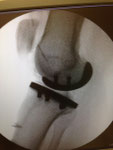

Auch bei dem künstlichen Ersatz des Kniegelenkes muss genau abgewogen werden, was eingentlich ersetzt werden muss. Je weniger ersetzt wird umso besser im Gesamtergebnis. Warum soll man das ganze Knie ersetzen, wenn nur der Knorpel unter der Kniescheibe zerstört ist (Bild 3 Kniescheiben - und Gleitlagerersatz). Anders bei schwerer Rheumazerstörung, bei der alle Bänder ausgelockert sind - hier wäre die normale Knieprothese auch locker (Bild 5 Lösung: achsgekoppelte Prothese). Ich versuche für meine Patienten das bestmögliche Implantat auszusuchen. Für Allergiker stehen spezielle titanbeschichtete Kniegelenke zur Verfügung.